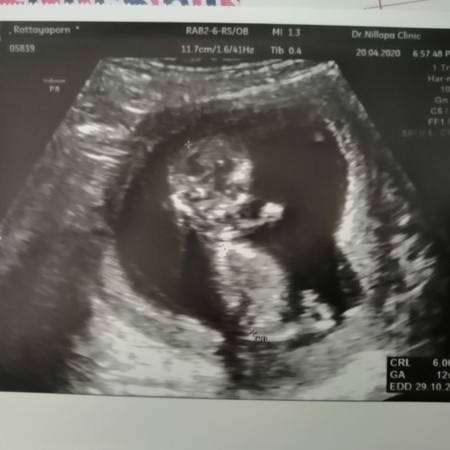

ตอนนี้ 13W แล้ว ไปซาวน์ตอน 8W หมอบอกเห็นตัวน้องชัดมารอบหน้าน่าจะรู้เพศ พอไปซาวน์ตอน 12W หมอบอกน้องลุกขึ้นนั่งมองไม่เห็น แต่เดาไว้ว่าน่าจะเป็นผู้ชาย เพราะแม่ไม่แพ้ท้อง แถมน้องตัวยาวด้วย พี่ที่ทำงานก็ทักว่าน่าจะผู้ชายค่ะ

บ้านนี้ไปซาวตอน12วีค น้องนั่ง หมอก็เดาว่าชายเหมือนกันคะ ไม่แพ้ท้อง ปัจจุบัน28วีคแล้วคะ

รู้เพศน้องรึยังคะตอนนี้ บ้านนี้หมอบอกว่าถ้าน้องเริ่มนั่ง อาจจะนั่งยาวไปจนคลอดเลย จนไม่รู้เพศ ตอนนี้บอกลูกก่อนนอนทุกคืนเลยค่ะว่าซาวน์รอบหน้าแม่ขอดูหน่อยนะ 😁

บ้านนี้16วีคยังไม่รู้เพศเลยค่ะน้องนอนคว่ำตลอดเลย

อายุครรภ์เท่ากันเลยค่ะ ไปดูเพศมาเมื่อวานมองเห็นเพศไม่ชัด